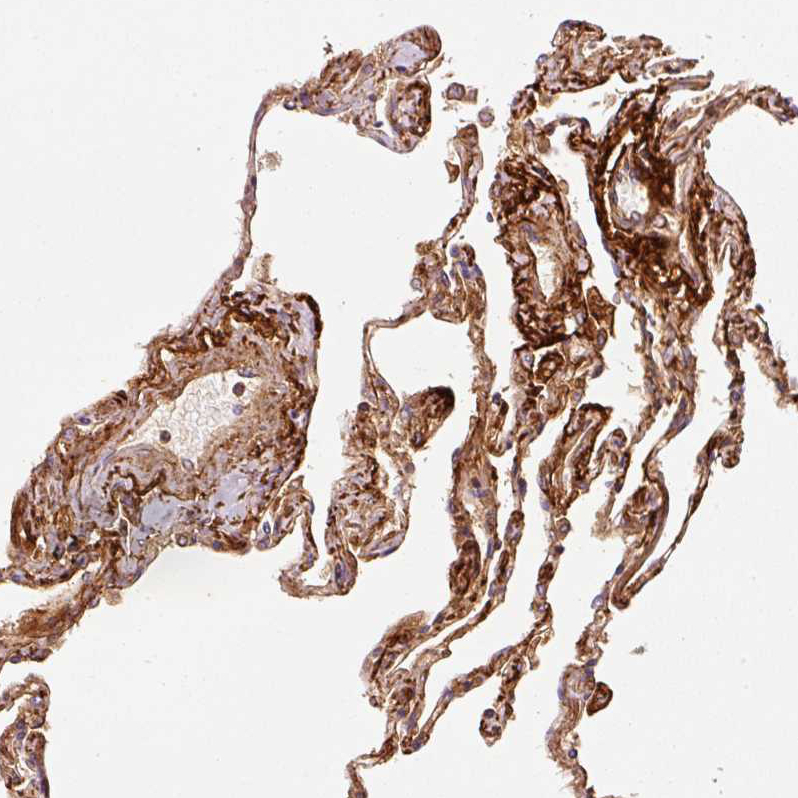

Immunohistochemical staining of human lung shows moderate extracellular space positivity in pneumocytes and macrophages.